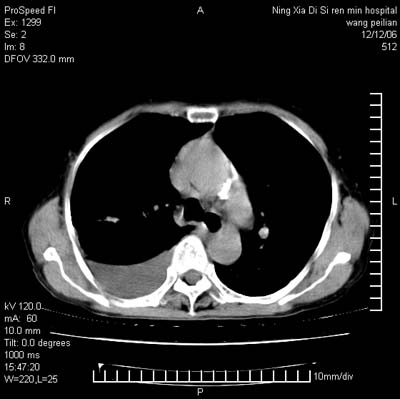

标题: CT5609:胸部:女77 病史不详

两肺可见多个大小不等的结节,左侧有胸水,纵隔淋巴结增大,考虑是细支气管肺泡癌

两肺尖纤维索状影,两下肺结节块状影,且有钙化灶,右胸腔积液。考虑肺结核并胸膜炎。

两肺尖纤维索状影,两下肺结节块状影,且有钙化灶,右胸腔积液。考虑肺结核并胸膜炎肺间质纤维化

考虑:1、慢性支气管炎合并全小叶型肺气肿、间质纤维化;

2、双肺结核;

3、右侧胸膜炎(积液)。

1、双肺继发型肺结核(以纤维、增殖灶为主);

2、右侧胸腔积液;

3、其余符合老年肺改变。

双肺见多个结节状及条索状影,双侧胸腔积液,右侧叶间积液,考虑结核性胸膜炎